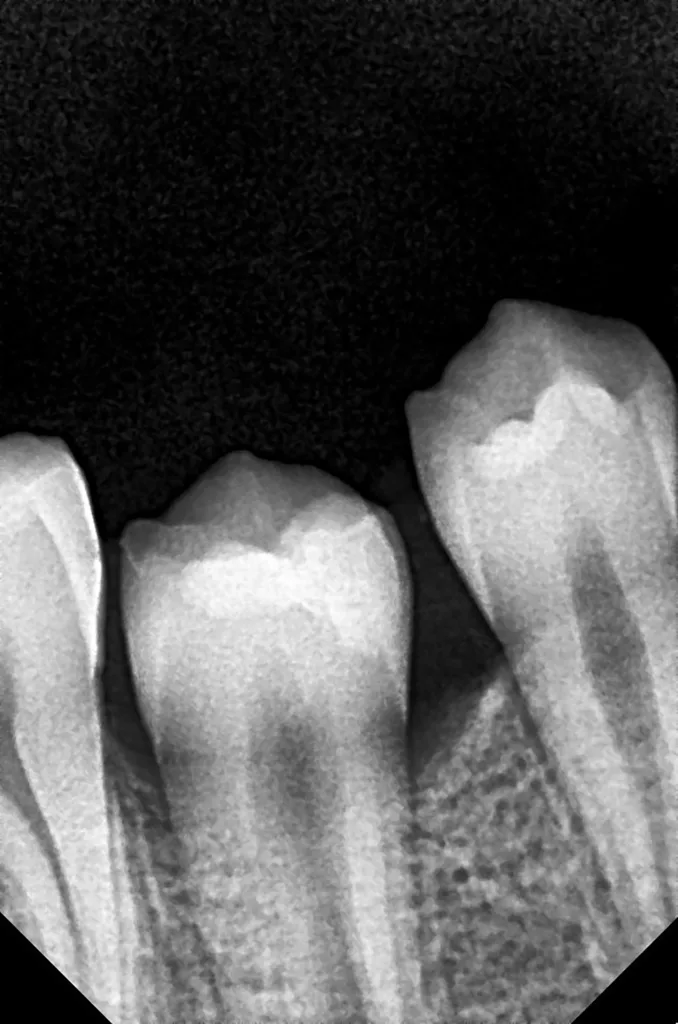

Bei routinemäßigen Röntgenkontrollen ergeben sich manchmal Zufallsbefunde unklarer Genese. So stellt sich beispielsweise bei der Betrachtung der Abbildung 1 die Frage, wie sich ein Zahnhartsubstanzdefekt so schnell entwickeln konnte. Ein weiteres Röntgenbild (Abb. 2), das vor dem Zahndurchbruch aufgenommen wurde, zeigt jedoch, dass es sich in diesem Fall nicht um Karies, sondern um die sogenannte präeruptive intrakoronale Resorption (PEIR) handelt. Für diesen Befund finden sich in der Fachliteratur auch noch andere Bezeichnungen wie „idiopathic external resorption of unerupted permanent teeth“ [1], „intra-follicular caries“ [2], „radiolucent lesions resembling caries“ [3], „occult caries“ [ 4] oder „pre-eruptive caries“ [5].

V. Slabkovskyi, O. LiutikovJahr vor dem Durchbruch des Zahnes 36.

Das fünfjährige Mädchen stellte sich 2017 zur jährlichen Routinekontrolle vor. Im Rahmen der Untersuchung wurden Röntgenaufnahmen der Milchmolaren gemacht (Abb. 2). Der klinische und radiologische Befund der vor uns früher gelegten Kompositfüllungen war gut, es wurde allerdings eine PEIR an den noch nicht durchgebrochenen ersten bleibenden Molaren festgestellt (Abb. 2). Den Eltern wurde empfohlen, sich unverzüglich bei Beginn des Durchbruchs der ersten Molaren erneut zur Behandlung vorzustellen. Ein Jahr später erschien die junge Patientin schmerzfrei zur Kontrolle. Der Zahn 36 war noch teilweise mit Gingiva bedeckt. Auf einer neuen Röntgenaufnahme (Abb. 1) wurde die PEIR-Läsion mit unveränderter Größe in pulpanahen Bereichen bestätigt (Grad 3 der Läsion nach Seow). Der Zahnschmelz sah intakt aus, es konnte kein pathologischer periapikaler Befund bei den noch nicht ausgewachsenen Zahnwurzeln festgestellt werden. Daraufhin wurden die verschiedenen Behandlungsmöglichkeiten von Fissurenversiegelung bis Vitalerhaltung der Zahnpulpa mit den Eltern des Kindes besprochen.